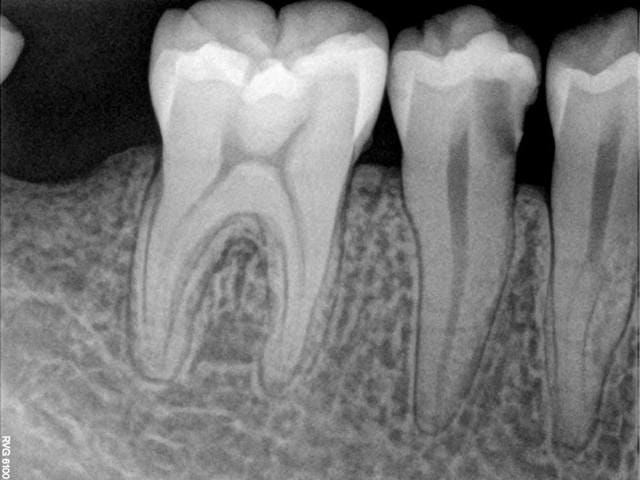

calcification canalaire

canal bifide ou 2 canaux .

comme le dis doctyoni, cette 44 a suremment une furcation basse et 2 canaux. on a l'impression de voir 2 apex...

En faisant une rx défilée pendant la bio de la 45 tu pourras confirmer

Fur cation très basse avec dédoublement canal aire .